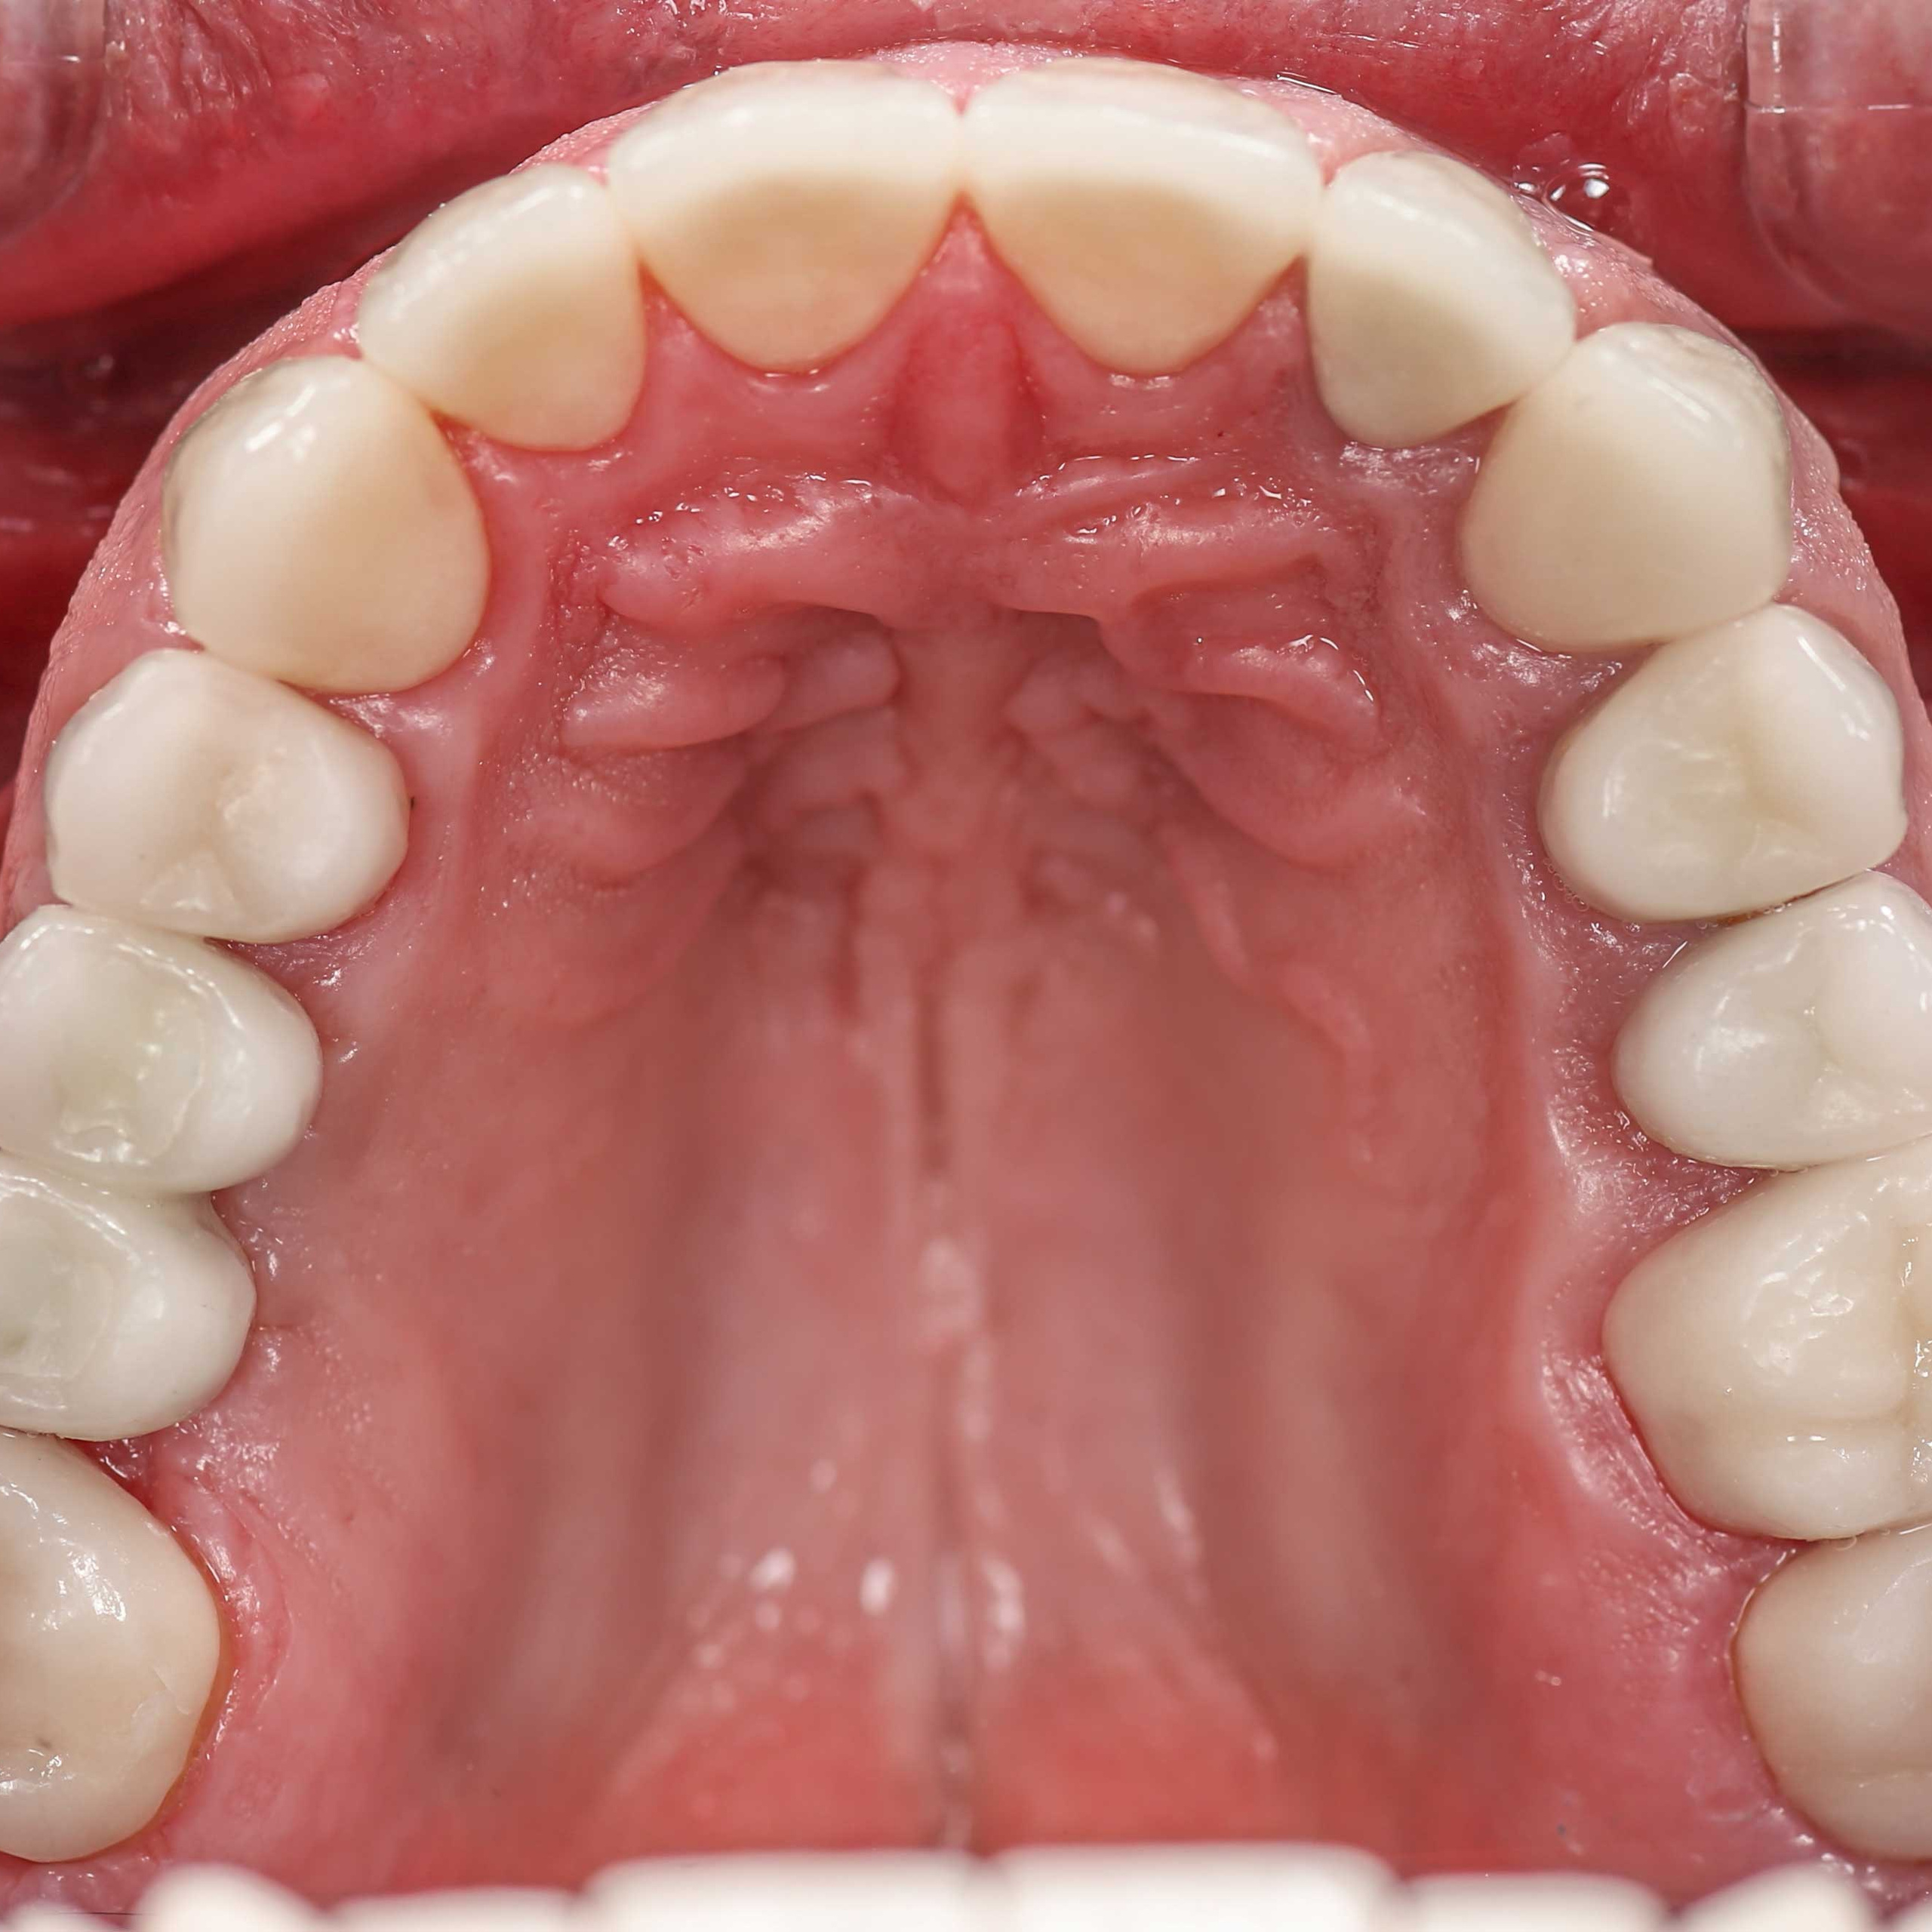

Фотографии учеников до обучения

Фотографии после обучения